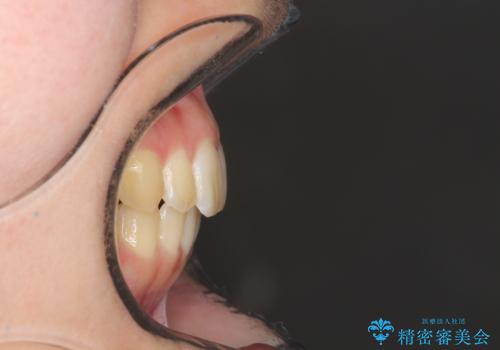

- 前歯が少し前に出ているのが気になるとのことで来院されました。

インビザラインにて上顎の歯を全体的に後方に移動させて前歯を引っ込める計画としました。